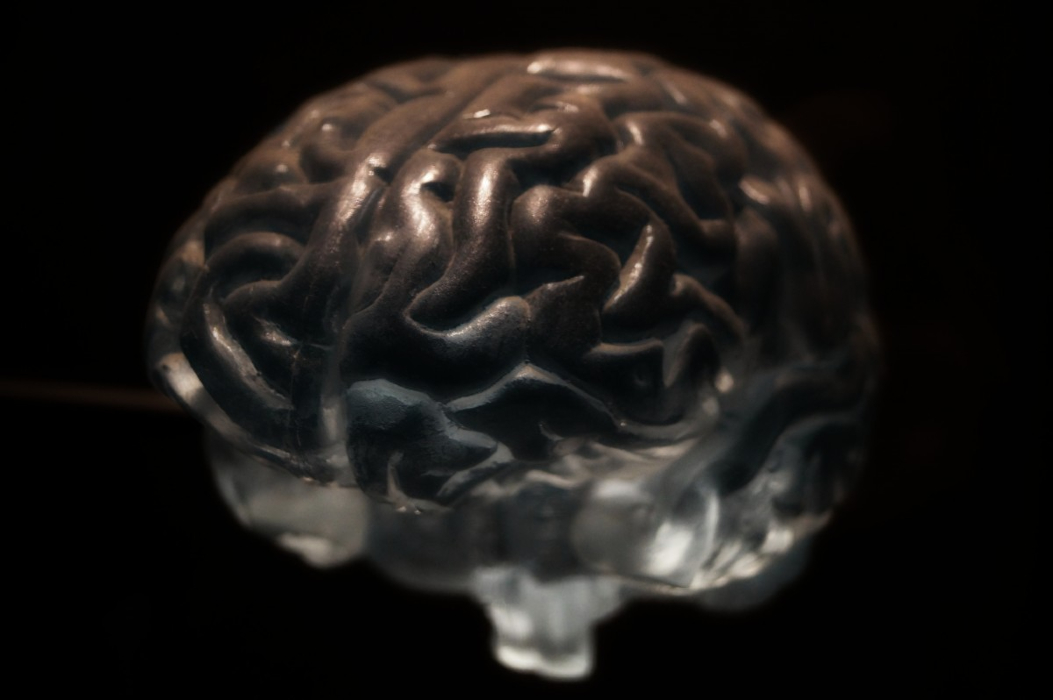

Πώς ένας παράλυτος κατάφερε να μιλήσει με ηλεκτρόδια στον εγκέφαλο

Ο Δρ Eddie Chang, νευροχειρουργός στο Πανεπιστήμιο της Καλιφόρνια, στην Ιατρική Σχολή του Σαν Φρανσίσκο, βοήθησε τον Pancho, έναν άνδρα παράλυτο από την ηλικία των 20 ετών, να μιλήσει μέσω ενός εμφυτεύματος στον εγκέφαλό του που συνδέεται με ένα πρόγραμμα υπολογιστή. Ο Πάντσο δε μπορούσε να μιλήσει από το 2003, όταν παρέλυσε μετά από ένα […]